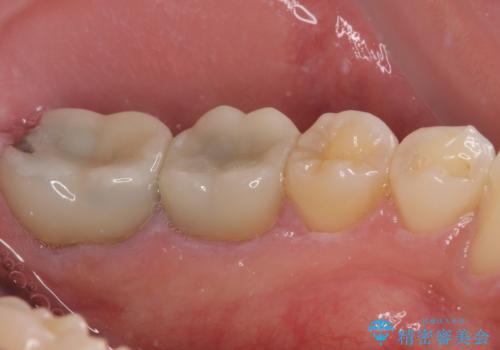

- 間もなく海外赴任という状況で奥歯のクラウンが割れてしまったとのことで来院された患者様です。

下顎の1番奥の歯であり、歯肉に覆われている部分が大きいためセラミックの十分な厚みが取れない状態でした。

強化セラミックを用いたオールセラミッククラウンにて補綴治療を行うこととしました。

十分な土台の高さを確保できない状態であったので、維持力のある土台の形態に整えることで、極力長持ちする治療を心がけました。